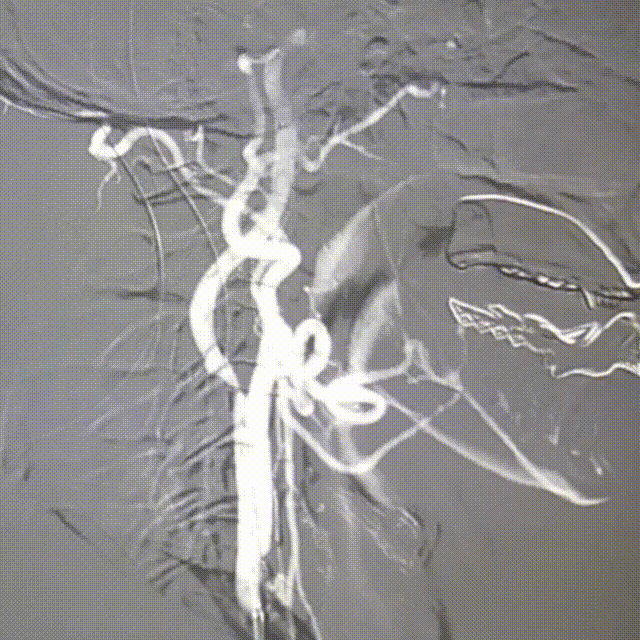

右颈内造影

动脉长鞘怎么置入桡路大腔,超薄无伤 | EasyMax™ Pro长鞘经桡入路辅助行颈内动脉支架植入术_https://www.jmylbn.com_新闻资讯_第2张

动脉长鞘怎么置入桡路大腔,超薄无伤 | EasyMax™ Pro长鞘经桡入路辅助行颈内动脉支架植入术_https://www.jmylbn.com_新闻资讯_第3张

DSA提示:右侧颈内动脉起始部重度狭窄(狭窄率约70%)。